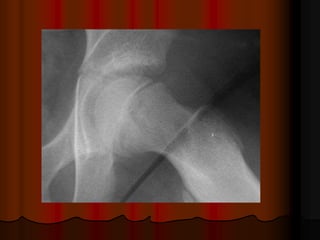

Imaging:

diminution of joint space, subchondral

bone sclerosis, osteophyte formation at

joint margin.